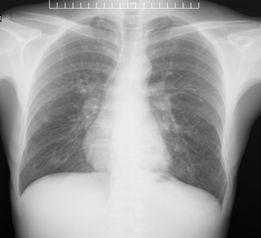

胸部X线片是肺隔离症影像学诊断的基本筛查方法。

它可以是这样的↓↓↓

图5左下肺野可见团块状密度增高影

也可以基本啥都没有↓↓↓

图6两肺纹理增多,左下肺见少许条索影,两肺门增浓

临床上常用胸片对肺内有无占位性病变进行初筛,但因其不能显示异常滋养动脉血管,无法对疾病进行定性诊断,常与肺部其他病变相混淆,临床诊断价值有限。